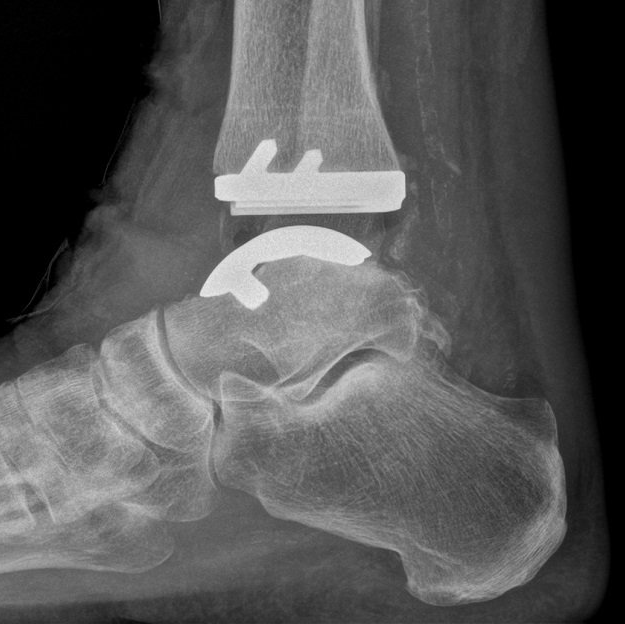

Ankle Replacement (Ankle Arthroplasty)

Replacing the ankle surfaces with metal and plastic has been available for many years but the results have been nowhere near as good as hip and knee replacement.

Ankle replacement technology continues to develop as our understanding of why these implants fail also develops. Better design, materials and patient-specific instruments are making the current generation of implants (2015 and beyond) more reliable (see images below).

Only small numbers are performed in Australia (729 in 2024). For comparison, 30000 hip and 33000 knee replacements are performed each year.

Ankle movement after ankle replacement is not normal. Some restriction and stiffness is common. Significant pain relief occurs in 70% of people.

All joint replacements eventually wear out and "fail". If an ankle replacement needs removing (revision), some are converted to fusion. Re-operation rate (20% at 10 years - for impingement, cysts, etc) and revision rate (14% at 10 years) are still higher than those of hip and knee replacement. Newer implants seem to be doing better.

Ankle replacement is offered to selected people with ankle arthritis. These include low-demand people, those older than 65 years, people with previously fused hindfoot joints, and those with rheumatoid or sero-negative inflammatory arthritis.